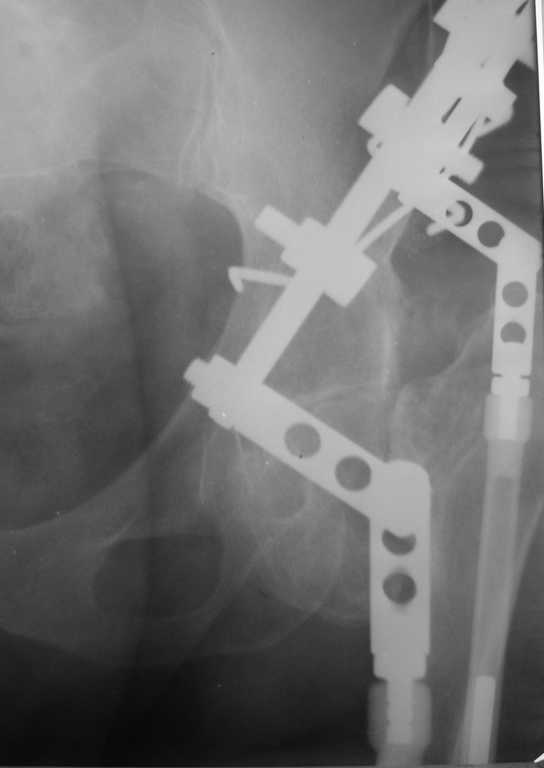

Приведу клинический пример несколько схожий с Вашим. Пациент 56 лет, 18 лет назад получил перелом шейки бедренной кости. Полноценного лечения не получил и остался с неопорным бедром. Укорочение было в районе 6-7 см. Первым этапом после миотомии приводящих мышц в теч. 2-х недель низвели бедро аппаратом Илизарова, далее сняв аппарат установили эндопротез гибридной фиксации (выраженный остепороз впадины ввиду отсутствия нагрузки). К сожалению, в процессе установки ножки эндопротеза произошёл перипротезный перелом медиальной стенки и профилактически мы наложили серкляжные швы. Контроль через 12 месяцев -укорочения нет, функция нормальная. Оперирован в 2005 году. с 2006 года к нам не обращался. АИФ